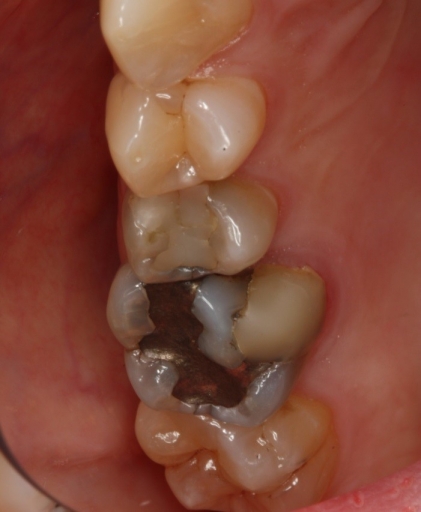

Here is a case in point: A long-term patient with an endodontically treated molar managed with a clinically acceptable crown presents with a new periapical asymptomatic lesion (Fig. 3). The diagnosis, based on radiographic and clinical history, is a recurrent periapical abscess due to microleakage. The tooth is adequately re-treated by a skilled endodontist and restored.

Less than 12 months later, the tooth develops a localized distal 9 mm periodontal pocket with bleeding on probing (Fig. 4). Upon extraction of the tooth, the diagnosis of a vertical distal root fracture is confirmed by direct observation under magnification. Therefore, it’s important to consider the possibility of occult root fractures being present whenever restorative dentistry is planned.

suggests a vertical fracture, combined with a localized 9 mm periodontal pocket.